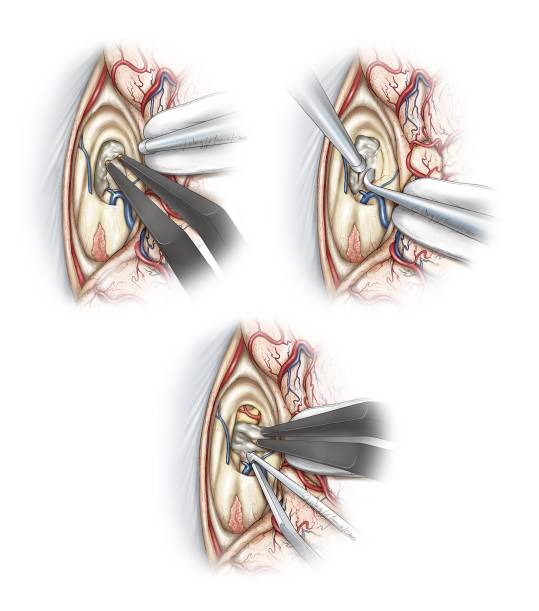

图10. 将覆盖在Monro孔和静脉角表面的脉络丛前方切断,然后轻柔的钝性分离和电凝。肿瘤通常会扩大室间孔,但是无法提供足以完整切除肿瘤的手术通道(Redrawn from Tew,van Loveren, Keller*)。

图11. 将隔静脉在临近室间孔处汇入丘纹静脉时分离并电凝,然后切断(上图)。下图提供了关于右侧脑室及相关解剖的术中照片。

图12.分离切断隔前静脉后,在丘纹静脉后方分离脉络裂可获得肿瘤和三脑室前中部的良好显露。在隔前静脉被电凝然后锐性切断后,向内侧轻柔地推移穹隆。通常在室间孔后缘和同侧丘纹静脉前缘之间有少许室管膜,可以采用显微剥离子切开室管膜之后用双极电凝颞轻轻的扩大(上图)。这一操作能明显扩大室间孔,有利于增加经三脑室的显露视野(下图为术中照片)。第三脑室左侧壁被标记(*)。